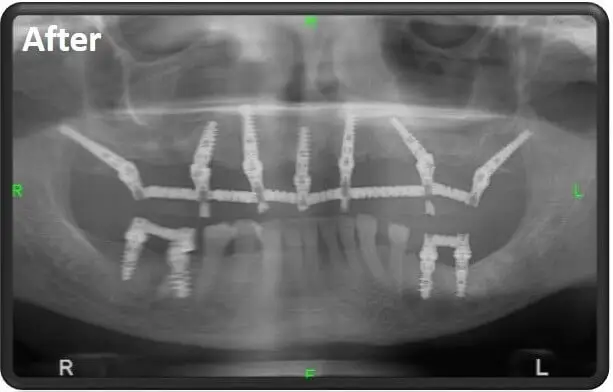

בניגוד לעבר, כשלאורך שנים התפישה הטיפולית הייתה שבמקום כל שן חסרה יש צורך למקם שתל דנטלי בדיוק במקום שבו היו ממוקמים שורשי השן, גישת ההעמסה המיידית שעליה מבוססת היכולת לבצע השתלות שיניים שינתה לחלוטין את התפישה הזו והראתה שמיקום נכון של שתלים דנטליים איכותיים מאפשר לרופא השיניים להסתפק בשישה ואפילו בארבעה שתלים בלבד (all on 4) ללסת שלמה.

לכן, פותחו שתלים שונים שמאפשרים לבצע חיבור אל עצמות הלסת גם בזוויות שיכולות להגיע עד ל-45 מעלות ומטרתן היא ליצור את העיגון הטוב ביותר בנקודה ובזווית הנכונים שבהם עצם הלסת היא העבה, החזקה והיציבה ביותר.

שתלים קורטיקליים הם למעשה שתלים ייעודיים לביצוע של השתלות שיניים בשיטה של העמסה מיידית.

יש להם חלק תחתון של הברגה אל העצם הקורטיקלית (עצם הלסת) וחלק עליון שיכול להתחבר במגוון רחב של זוויות אל הגשר שעליו ממוקמים הכתרים.

את השתלים הקורטיקליים ניתן להשתיל בזוויות לא ישרות שמגיעות עד ל-45 מעלות. למידע נוסף על שתלים קורטיקליים